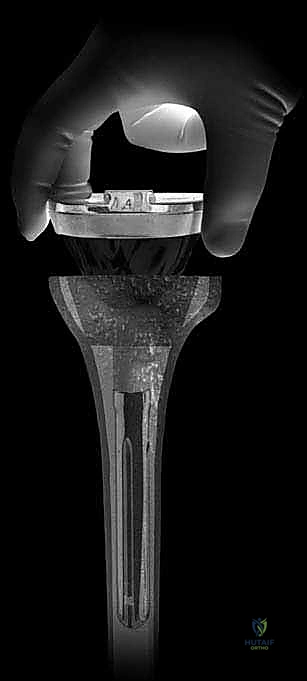

هنا جاءت الثورة الطبية المتمثلة في الدعامات المعدنية (Metallic Augments). هذه الدعامات مصنوعة من سبائك التيتانيوم أو التانتالوم (Tantalum). التانتالوم، المعروف تجارياً باسم "المعدن التربيقي" (Trabecular Metal)، يتميز بكونه مسامياً بنسبة تصل إلى 80%، مما يحاكي تماماً بنية العظم البشري الإسفنجي.

* إذا كان العيب سطحياً وفي جهة واحدة، تُستخدم الكتل أو الأوتاد المعدنية (Wedges/Blocks) التي تُثبت بأسفل الغرسة الجديدة.

* إذا كان العيب كبيراً وعميقاً في المركز، تُستخدم المخاريط أو الأكمام المسامية (Cones/Sleeves). يتم حفر العظم التالف بشكل هندسي دقيق ليحتضن هذا المخروط المعدني الذي يوفر أساساً صخرياً متيناً.

5. استخدام السيقان المعدنية للتثبيت (Stem Fixation)

بما أن العظم العلوي للساق ضعيف، لا يمكن الاعتماد عليه وحده لتثبيت المفصل. لذلك، يتم إدخال ساق معدنية طويلة (Stem) متصلة بالغرسة الجديدة وتمتد إلى داخل القناة النخاعية لعظم الساق (Diaphysis). هذا الساق ينقل الضغط والوزن من منطقة المفصل الضعيفة إلى العظم القوي في منتصف الساق، مما يضمن ثباتاً ميكانيكياً فائقاً.

7. التثبيت النهائي والإغلاق (Final Implantation and Closure)

بمجرد التأكد من مثالية القياسات، يتم تثبيت المكونات الأصلية باستخدام أسمنت عظمي خاص يحتوي على مضادات حيوية للوقاية من العدوى. يتم غسل المفصل جيداً، وإغلاق الجرح بطبقات تجميلية دقيقة لضمان التئام سريع وتقليل الندبات.